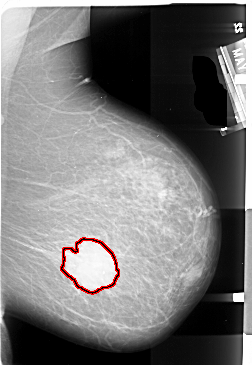

A_1004_1.RIGHT_CC

FILE: A_1004_1.RIGHT_CC.OVERLAY

TOTAL_ABNORMALITIES 1

ABNORMALITY 1

LESION_TYPE MASS SHAPE IRREGULAR MARGINS ILL_DEFINED

ASSESSMENT 5

SUBTLETY 5

PATHOLOGY MALIGNANT

TOTAL_OUTLINES 1

BOUNDARY